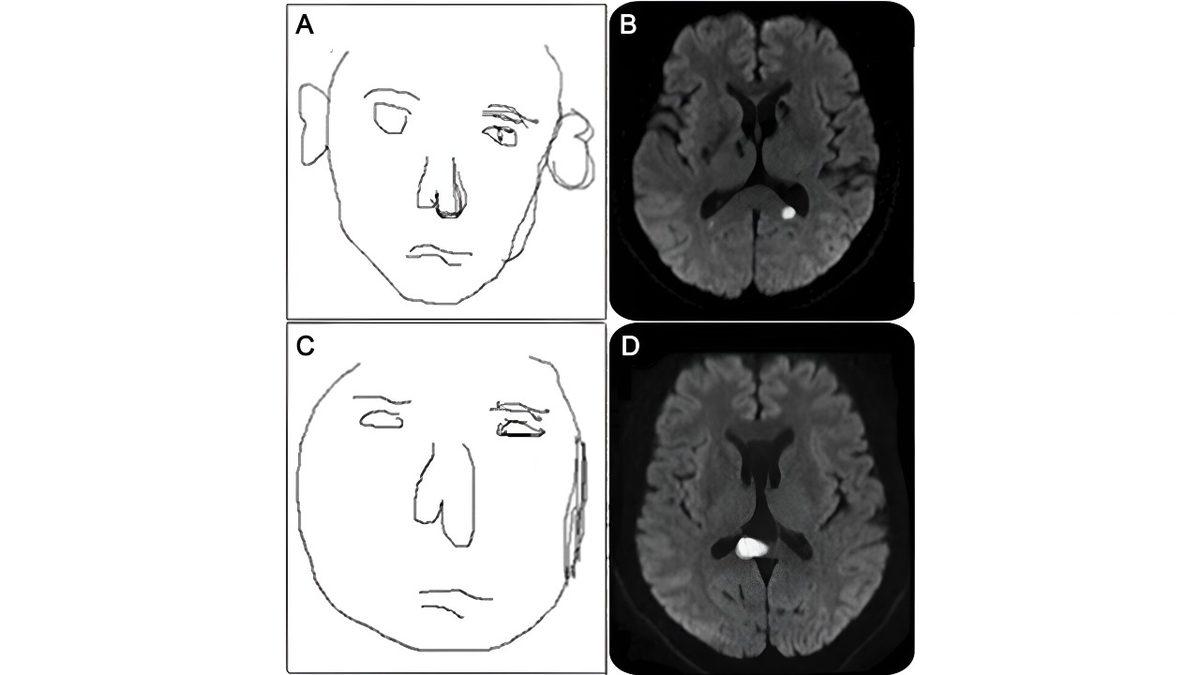

Prosopometamorfopsisi olan bir kişi; başkasının yüzüne baktığında yüz hatlarının aniden değiştiğini, gözlerinin birbirine yaklaşıp uzaklaştığını, çene çizgisinin giderek genişlediğini, şişikler çıktığını, cildinin hareket edip parladığını görebilir. Aynı durumu, aynada kendi yüzüne bakarken de yaşayabilir elbette.

Bozukluğa dair kesin bir neden hâlâ bulunamadı fakat çeşitli potansiyel teoriler var. Tahmin edebileceğiniz üzere LSD ve benzeri halüsinojenler ile ortaya çıkabilir fakat inme, felç, beynin bölümlerinden birine alınan hasarla ya da beyindeki bazı bölümlerdeki anormallikler yüzünden de görülebilir. Örneğin “superior temporal sulkus”; yüz ifadelerini, özellikle gözlerle ilgili ifadeleri işlerken aktive olur ve buranın hasar alması prosopometamorfopsiye yol açabilir.